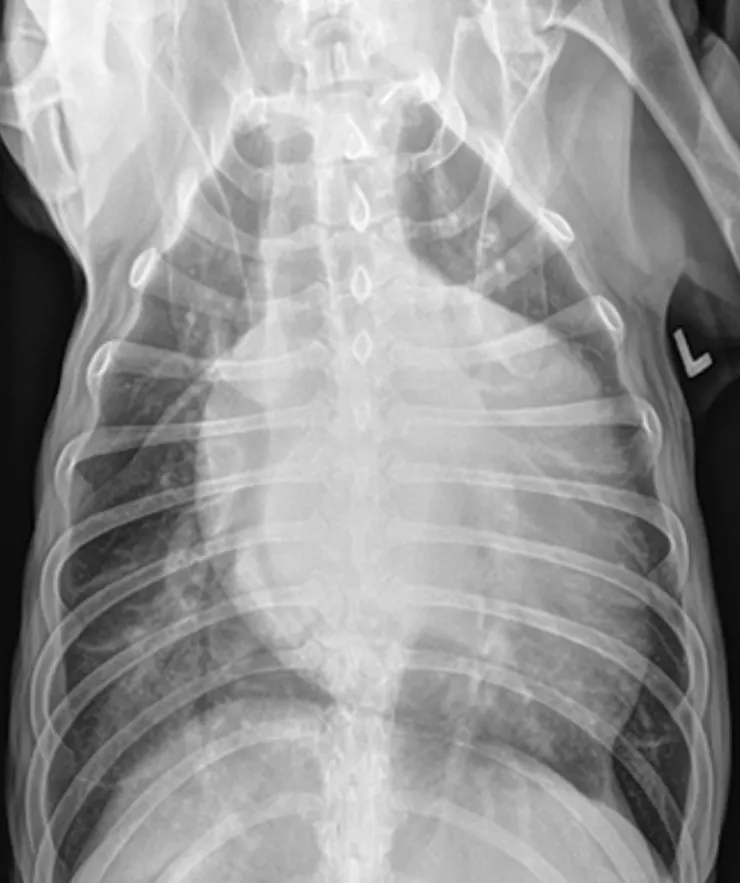

➡️在明顯的病例上, 的確當我們看到擴張的左心房與肺積水加上明顯的心雜音, 就可以診斷是心臟病造成的肺積水。但是總是有遇到一些比較難以區分的時候, 造成的原因有可能是當我們拍xray 時剛好拍到狗狗吐氣時, 肺就會看起來比較實質 (比較“白“)但並不是真的有肺積水。或是遇到年紀大且體型又比較胖的動物,肺部影像當然也會看起來比年輕又瘦的狗“白“。另外像是如果動物同時又有肺臟疾病時肺部影像也會比較難區分。所以如果我們沒有看到明顯左心房變大且肺積水出現在心因性肺積水常出現的位置, 就需要更多的檢查去輔助判斷。

心臟擴張 肺積水

心臟擴張肺積水